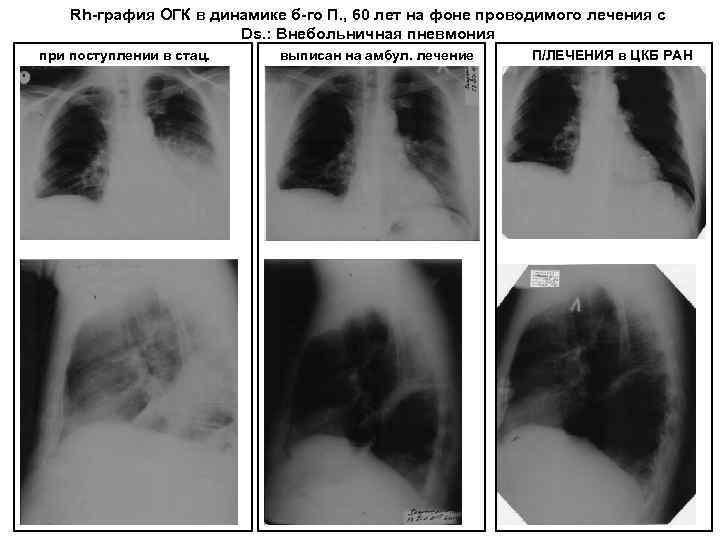

Rh-графия ОГК в динамике б-го П. , 60 лет на фоне проводимого лечения с Ds. : Внебольничная пневмония при поступлении в стац. выписан на амбул. лечение П/ЛЕЧЕНИЯ в ЦКБ РАН